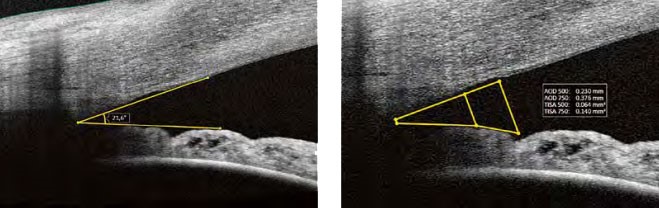

Програма для аналізу переднього сегмента дозволяє виміряти відстань між двома точками, довільні кути, а також значення AOD (відстань відкриття кута) та TISA (іридо-трабекулярний простір)